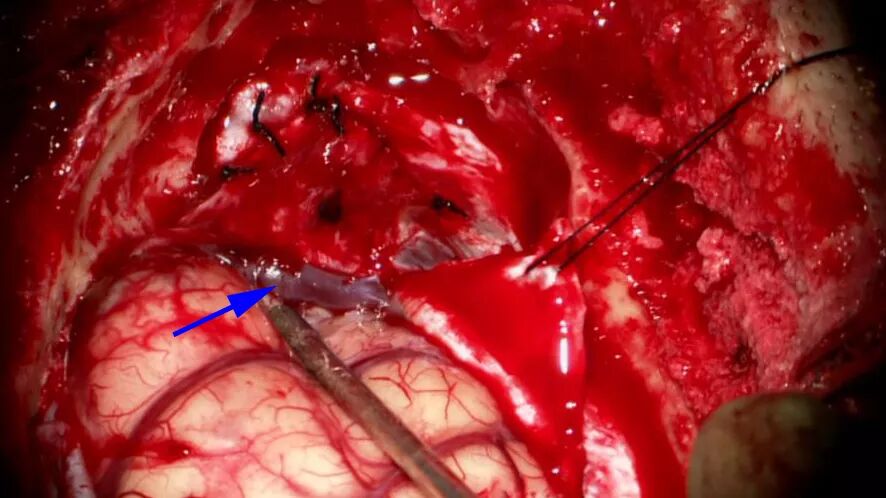

![]()

图7. 右侧横窦与乙状窦交接处撕裂,将毗邻硬脑膜翻转包裹撕裂处后缝合。Labbe静脉(箭头)得以保留。